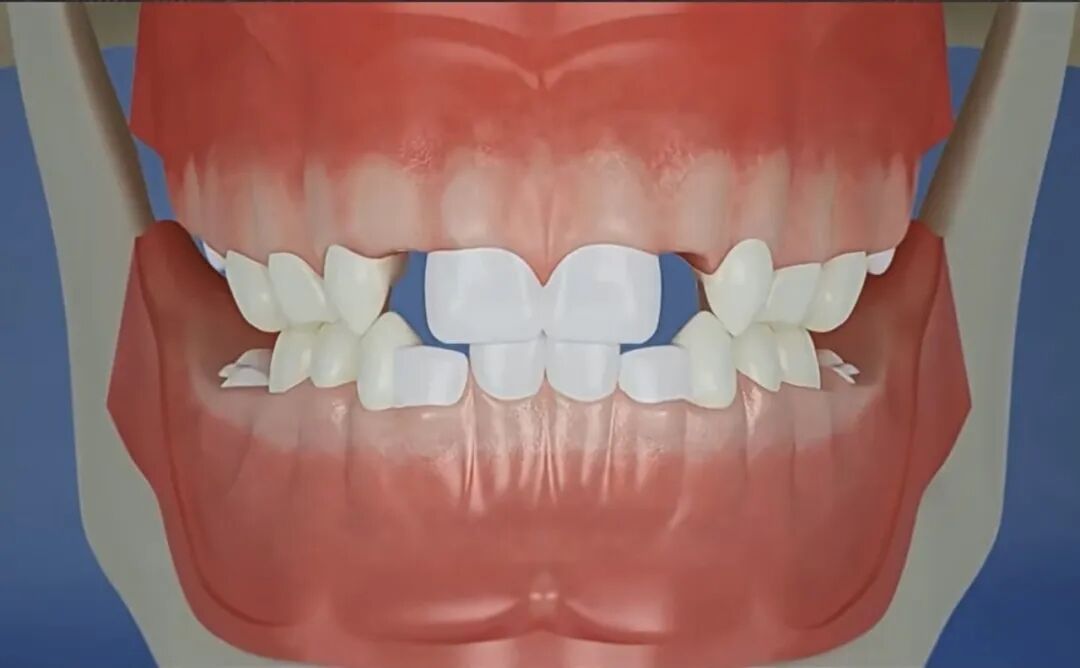

Q6.出现“双排牙”咋办?到底要不要拔?

“双排牙”又叫“乳牙滞留”,简单说就是新牙已经长出来了,旧牙还不肯掉。

曲面断层片怎么看换牙与身高有关吗?关于孩子换牙的所有疑问一篇说清_https://www.jmylbn.com_新闻资讯_第14张

关于双排牙到底要不要拔,是一个有点争议的话题。

国内外学者有争议⚠️

国内教科书上建议尽早拔除滞留乳牙,尤其是上颌“双排牙”。

而国外学者Gellin等监测了44名儿童,发现95%的下颌恒中切牙在8岁2个月前都能自行调整到正确位置,下颌侧切牙至少在8岁4个月时能自行调正,考虑到双排牙可能会造成家长的焦虑情绪,他们认为7岁半前出现“双排牙”没必要拔除。其他考虑还包括第一次就诊时就拔牙可能会影响孩子和医生建立融洽关系等。

所以,双排牙要不要拔,并非简单的Yes or No,下面分享一下我在临床工作中的一些观点:

1. 首先,可以肯定的是,及时拔掉滞留乳牙有利于新牙往前排齐和牙齿的清洁,对孩子的口腔健康没有坏处。

2. 最终新牙能否完全排齐,主要看乳牙是否“有缝”。乳牙“有缝”是牙弓位置充足的重要标志之一。

对于下颌牙齿,只要牙弓位置充足,滞留的乳牙无论是晚一点自行脱落还是提前拔除,恒牙都能在之后的数月内往前排齐。而如果牙弓空间不够,即使提前拔除了滞留乳牙,恒牙最终仍可能无法完全排齐。

曲面断层片怎么看换牙与身高有关吗?关于孩子换牙的所有疑问一篇说清_https://www.jmylbn.com_新闻资讯_第15张

曲面断层片怎么看换牙与身高有关吗?关于孩子换牙的所有疑问一篇说清_https://www.jmylbn.com_新闻资讯_第16张

图注:左图:乳前牙有缝,右图:乳前牙没缝

3. 上颌“双排牙”应尽早拔除,避免造成“地包天”。

曲面断层片怎么看换牙与身高有关吗?关于孩子换牙的所有疑问一篇说清_https://www.jmylbn.com_新闻资讯_第17张